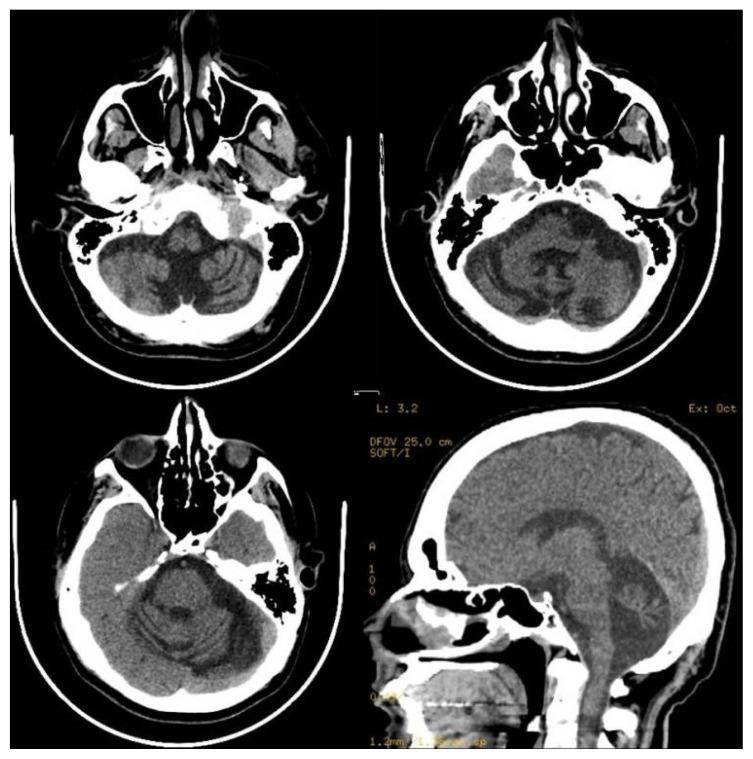

Phenytoin (diphenylhydantoin) is a widely used antiepileptic drug for controlling both generalized and partial seizures. Reversible cerebellar symptoms, including cerebellar ataxia, have been recognized as an adverse event of phenytoin use for many years. On the other hand, cerebellar degeneration has been reported with chronic use in an epileptic patient treated with this drug. We are reporting an interesting case of phenytoin induced acute pan-cerebellar syndrome with cerebellar atrophy on neuro-imaging that improved many years after discontinuation of the drug. Discontinuation of phenytoin may give a chance for the patient to recover slowly, months after stopping the drug. It is very important for the attending neurologist to educate the patients and their families on some common clinical manifestations suggestive of drug toxicity and perform a regular follow-up and clinical examination at regular intervals.

苯妥英钠(二苯乙内酰脲)是一种广泛用于控制全身性和部分性癫痫发作的抗癫痫药物。包括小脑共济失调在内的可逆性小脑症状,多年来一直被认为是使用苯妥英钠的不良事件。另一方面,有报道称在使用该药物治疗的癫痫患者中,长期使用会导致小脑变性。我们报告了一例有趣的病例,该病例为苯妥英钠诱发的急性全小脑综合征,神经影像学显示有小脑萎缩,在停药多年后有所改善。停用苯妥英钠可能会给患者一个缓慢恢复的机会,在停药数月后逐渐恢复。对于主治神经科医生来说,对患者及其家属进行有关提示药物毒性的一些常见临床表现的教育,并定期进行随访和临床检查非常重要。